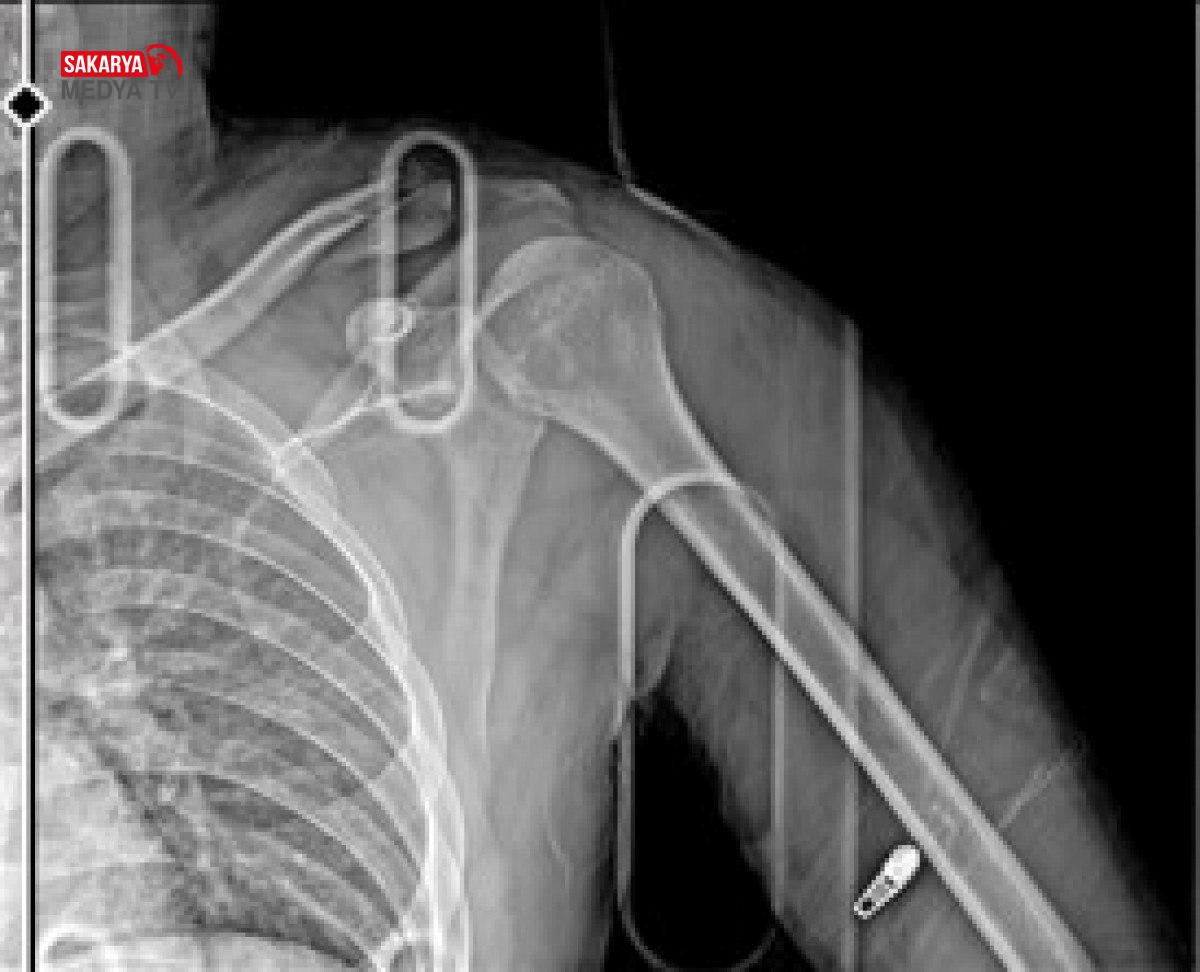

OMZUNDA KALICI HASAR OLUŞTU

Çiçek, yaralı halde hastaneye kaldırılırken, sağ omzundan ameliyat oldu. Çiçek’in platin takılan kolunda kalıcı hasar oluştu. Hastanedeki tedavisinin akabinde konutunda istirahate çekilen Çiçek, işine devam edemeyeceğini söz ederek, adaletin yerini bulmasını istedi. Çiçek, araba şoförü Y.Y.’den şikayetçi oldu.